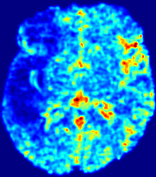

TimeSlice(i)(ii)(iii)(iv)(v)(vi)Refer to caption00777141414212121282828353535Refer to caption(a)(b)Refer to captionRefer to captionRefer to captionRefer to captionRefer to captionRefer to captionRefer to captionRefer to captionRefer to captionRefer to captionRefer to captionRefer to captionRefer to captionRefer to captionRefer to captionRefer to captionRefer to captionRefer to caption(a)(b)Refer to captionRefer to captionRefer to captionRefer to captionRefer to captionRefer to captionRefer to captionRefer to captionRefer to captionRefer to captionRefer to captionRefer to captionRefer to captionRefer to captionRefer to captionRefer to captionRefer to captionRefer to caption(a)(b)Refer to captionRefer to captionRefer to captionRefer to captionRefer to captionRefer to captionRefer to captionRefer to captionRefer to captionRefer to captionRefer to captionRefer to captionRefer to captionRefer to captionRefer to captionRefer to captionRefer to captionRefer to caption(a)(b)Refer to captionRefer to captionRefer to captionRefer to captionRefer to captionRefer to captionRefer to captionRefer to captionRefer to captionRefer to captionRefer to captionRefer to captionRefer to captionRefer to captionRefer to captionRefer to captionRefer to captionRefer to caption(a)(b)Refer to captionRefer to captionRefer to captionRefer to captionRefer to captionRefer to captionRefer to captionRefer to captionRefer to captionRefer to captionRefer to captionRefer to captionRefer to captionRefer to captionRefer to captionRefer to captionRefer to captionRefer to caption(a)(b)Refer to captionRefer to captionRefer to captionRefer to captionRefer to captionRefer to captionRefer to captionRefer to captionRefer to captionRefer to captionRefer to captionRefer to captionRefer to captionRefer to captionRefer to captionRefer to captionRefer to captionRefer to caption

Figure 5: Predicted concentration time series for the same patient shown in Fig. 3, where (i)-(vi) correspond to slices #1-6 respectively. Each grouped row displays (a) the measured concentration image sequences and (b) the predicted concentrations at corresponding time points.

3.2 Predicted CA Concentration

To better illustrate the prediction accuracy, and therefore the estimation accuracy of 𝐕𝐕{\bf V} and D𝐷{D}, of PIANO, we provide the corresponding predicted time-series of CA concentration images in Fig. 5 and Fig. 6 for the same patients in Fig. 3 and Fig. 4, respectively. We see that PIANO is capable of predicting the CA concentration given their initial state, indicating its ability to successfully capture 𝐕𝐕{\bf V} and D𝐷{D}. Note that although the concentration values for these two patients differ considerably, caused by the different total volume of injected CA, PIANO is still able to provide plausible estimates.